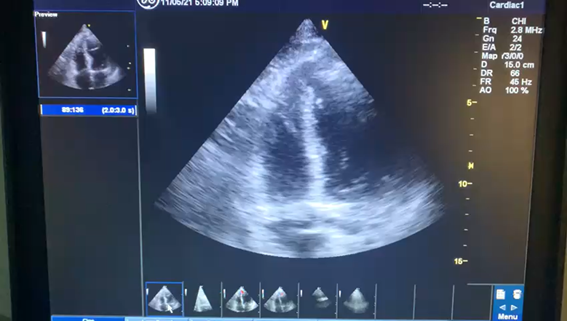

Ecocardiograma: evidencia o defeito do septo interventricular em (A) e o shunt da esquerda para a direita em (B):

A: defeito apical do septo interventricular (seta azul)